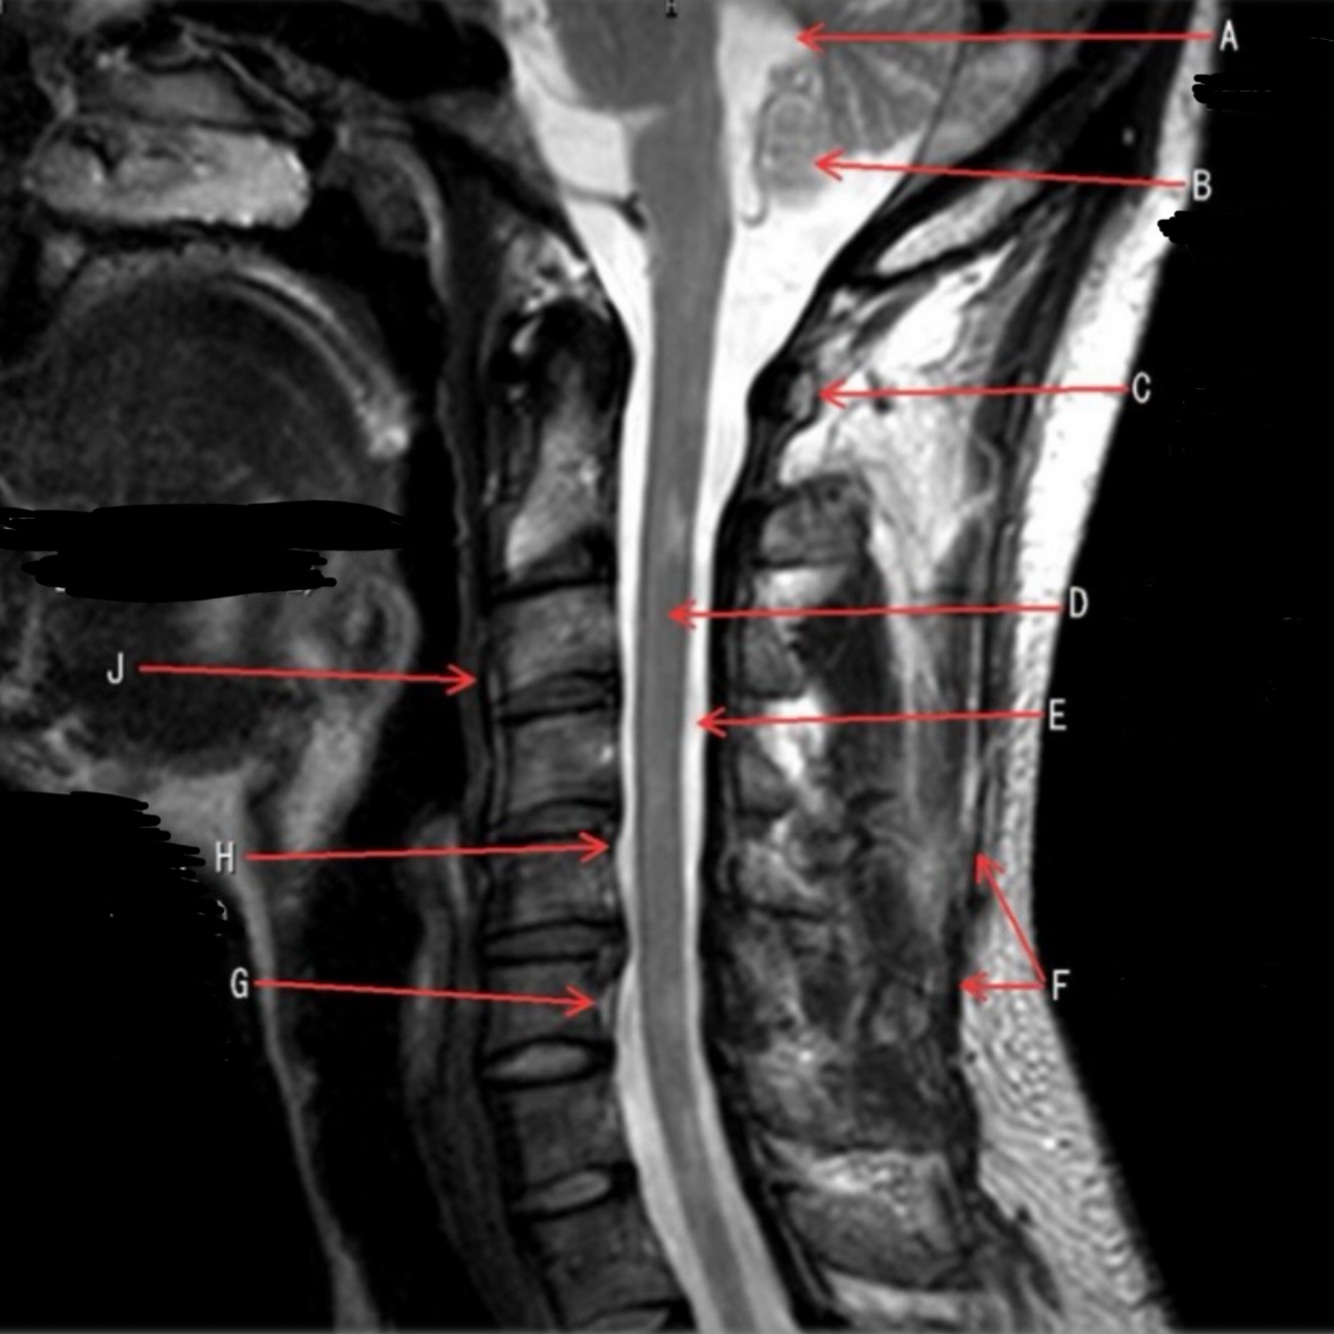

1

What is letter A?

4TH VENTRICLE

2

What is letter B?

CEREBELLUM

3

What is letter C?

POSTERIOR ARCH OF C1

4

What is letter D?

5

What is letter E?

CSF

6

What is letter F?

SPINOUS LIGAMENT

7

What is letter G?

VENUS PLEXUS

8

What is letter H?

POSTERIOR LONGITUDINAL LIGAMENT (PLL)

9

What is letter J?

ANTERIOR LONGITUDINAL LIGAMENT (ALL)